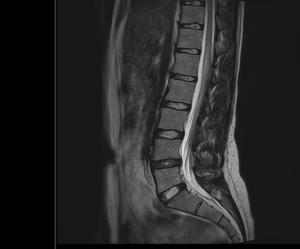

Sofand Skrevet 9. mars 2019 Skrevet 9. mars 2019 Er det noen innenfor faget som ser hva dette MR bildet av ryggen viser?

Skandinav Skrevet 10. mars 2019 Skrevet 10. mars 2019 Bildet er ikke det tydeligste, men ser ut som en gammel prolaps mellom L4 og L5.

Sofand Skrevet 10. mars 2019 Forfatter Skrevet 10. mars 2019 Bildet er ikke det tydeligste, men ser ut som en gammel prolaps mellom L4 og L5. Tusen takk for svar! Sier disse bildene noe mer kanskje?